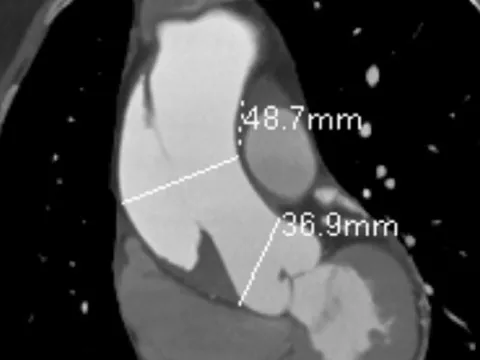

TPHCM: Người phụ nữ suýt tử vong, dấu hiệu cảnh báo chỉ đau ngực

TPO - Nữ bệnh nhân nhập viện trong tình trạng bị đau ngực kéo dài không rõ nguyên nhân. Qua chẩn đoán hình ảnh, bác sĩ phát hiện bệnh nhân bị lóc thành động mạch, nguy cơ đột tử bất kỳ lúc nào.